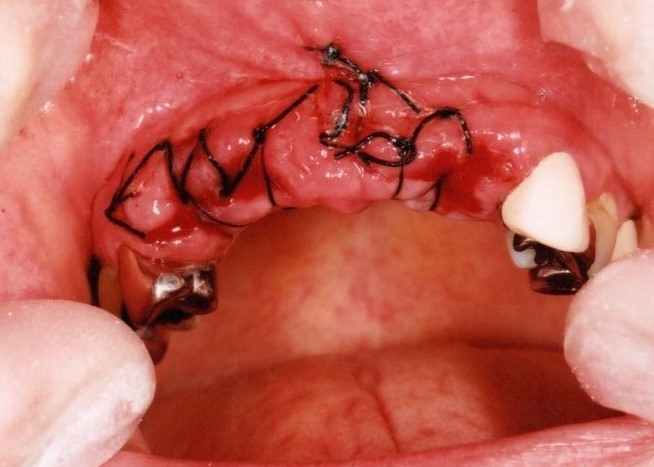

ブリッジの欠点

少ない本数の土台で支えるブリッジの場合、過重負担のため、支える歯がむし歯や歯槽膿漏で悪くなると、ブリッジ全て失う可能性があります。

特に保険で作られた適合があまいブリッジは約7年で50%が悪くなります。

少ない本数で支えられ作られたブリッジ、見た目はよいですが…

少ない支えで過重負担となり、支える歯ごと抜けてしまいました。

その結果、多数の歯を一度に失うことになりました。